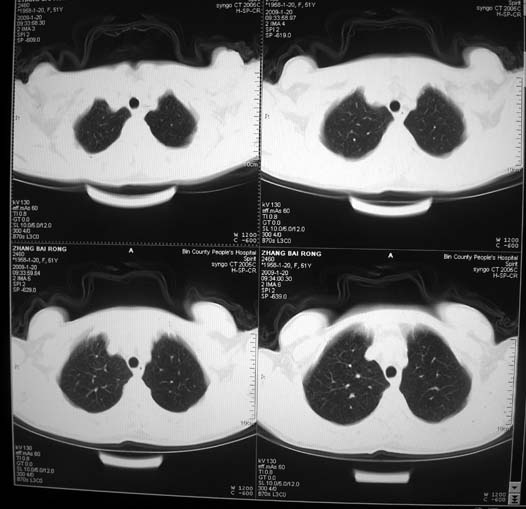

以下是引用zsl6918在2009-1-20 17:30:00的发言:[br]支持右肺下叶背段周围型肺癌,隆突下淋巴结肿大

以下是引用宇宙ct在2009-1-20 16:28:00的发言:[br]周围性肺癌\\纵隔淋巴转移

以下是引用sos.la在2009-1-20 18:01:00的发言:[br]实质性密度均匀肿块.边界清晰,浅分叶.无明显毛刺征,离胸膜近却无胸膜凹陷征,发生在段及段以下支气管,病灶直径远远超过此位置支气管管径而无阻塞征象,7#淋巴结肿大,病理是小细胞未分化癌(局限期)可能性最大.